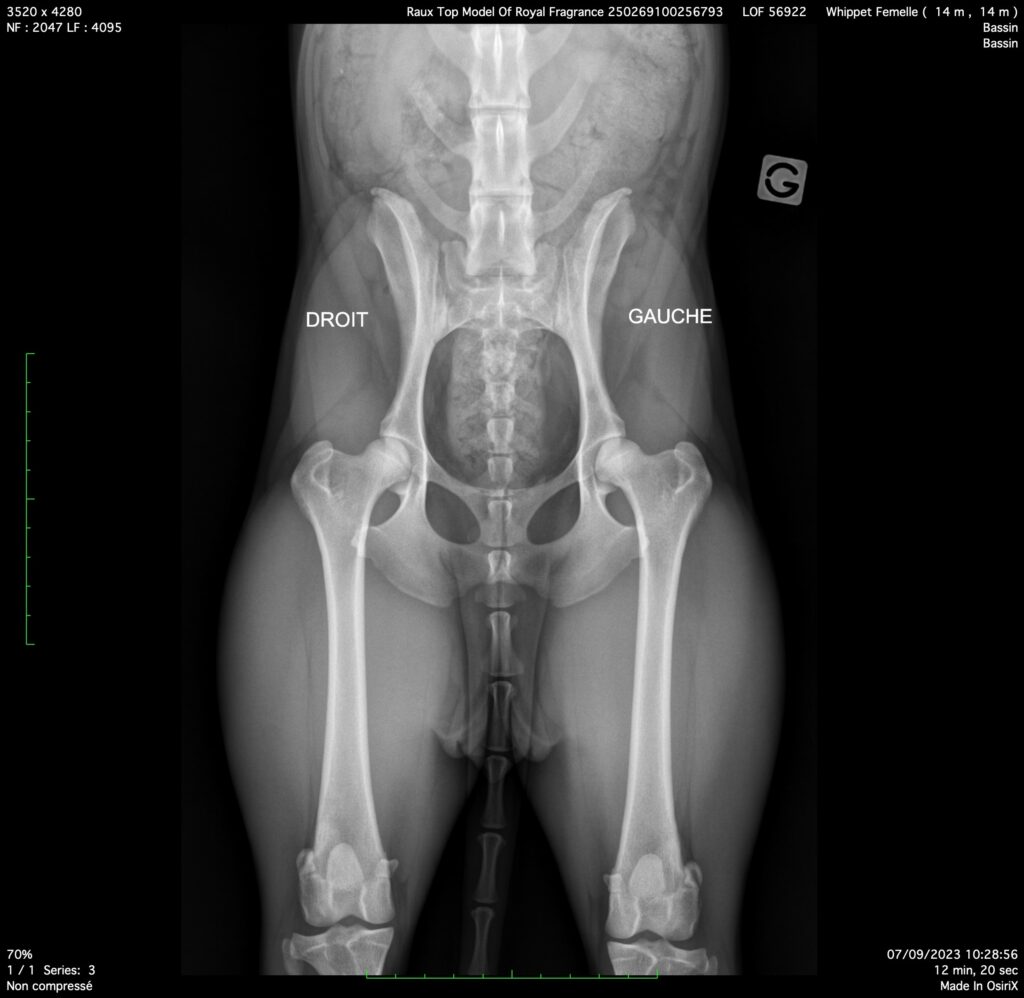

J’ai donc décidé d’affronter le problème, et de mettre en place des tests de santé. Pourtant, officiellement en France, la Société Centrale Canine et le club de race considèrent que le whippet n’est prédisposé à aucune maladie en particulier et ne poussent donc pas à faire des tests de santé.

Mais lorsque l’on traverse les frontières et que l’on regarde ce qui se passe ailleurs, on découvre que dans les pays voisins les éleveurs sont encouragés à rechercher certaines maladies occulaires, cardiaques et osseuses.

Initier des tests de santé vis à vis de ces maladies a soulevé de nombreux points d’interrogations / problèmes :

- la question du coût : certains tests coutent 100 euros, d’autres plusieurs centaines d’euros et lorsque l’on a une 15 aine de chiens dans l’élevage comme c’est mon cas, il s’agit d’emblée d’un investissement de plusieurs milliers d’euros ! Alors j’ai décidé d’y aller par étape, de commencer par les maladies les plus graves, et d’élargir petit à petit aux autres maladies. En 2 ou 3 ans j’ai réussi à tester tout le monde contre toutes les maladies que je m’étais fixée de surveiller ! J’ai aussi augmenté le prix des chiots pour financer ces tests, mais j’estime que c’est une cause d’augmentation du prix qui est légitime !

Comme tout n’est jamais tout rose, certains tests sont revenus positifs, des anomalies ont été trouvées, et me conduisent donc à revoir mes projets d’élevage, à dire adieu à certains mariages que j’avais prévu et même à retraiter certains chiens. Je reste malgré tout discrète sur ces cas positifs simplement parce que je ne veux pas être responsable du dénigrement de certaines lignées. Mon objectif n’est pas et ne sera jamais de pointer du doigt des affixes ou des lignées. Mon objectif est uniquement de tendre vers des lignées les plus saines possibles sur le plan de la santé !